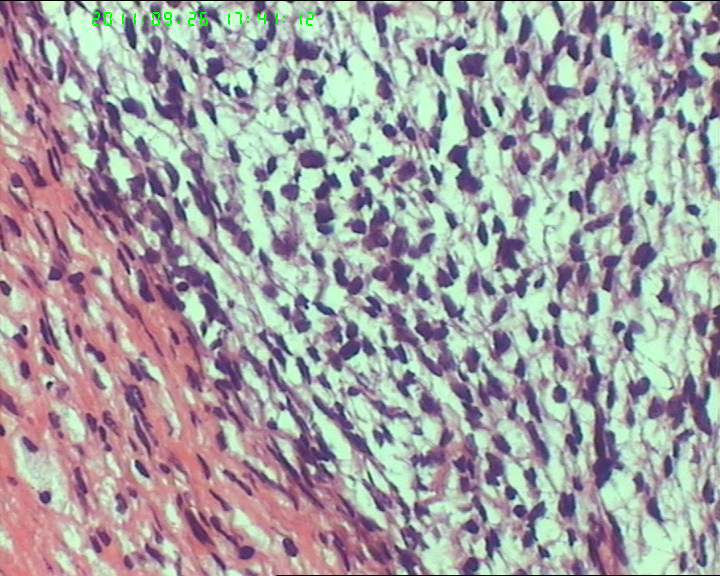

灰白不整形肿物一个,大小18*15*9cm,表面结节状,包膜完整,切面灰白,中央可见坏死区,质软,范围5*4cm。其余切面多彩 部分半透明状 质中。

鉴别诊断排排队:1、GIST,2、MPNST,3、去分化脂肪肉瘤,4、恶性间皮瘤,5、恶性SFT,6、平肉

主要考虑前二者。CD34,CD117,S-100,BCL-2,SMA, D2-40,CR, VIM. 结果如何?请楼主揭谜底吧。